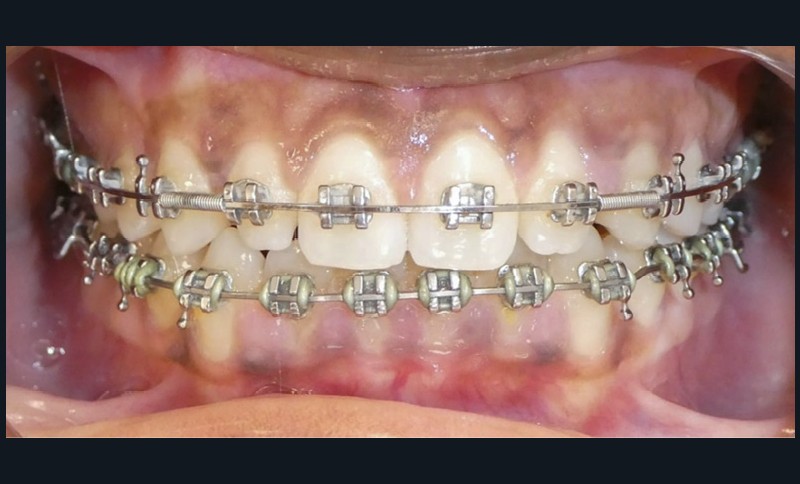

Finitions et intercuspidation

La correction des axes dentaires et les finitions sont réalisées sur arc acier 0,019×0,025’’. Des TIM d’intercuspidation sous forme de triangles latéraux de classe I (3/16 – 3,5 oz) permettent de parfaire l’occlusion.

Les objectifs de traitement ont été atteints.

L’esthétique du sourire a été améliorée avec l’augmentation de la visibilité des dents maxillaires, ainsi que la restauration des incisives latérales au composite.

Le profil est plus harmonieux grâce à une diminution de la prochéilie mandibulaire par redressement de l’incisive mandibulaire (fig. 16- 18).